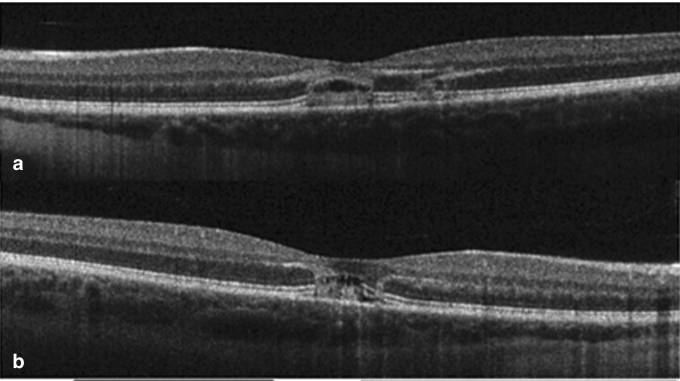

На дне глаза образовалось небольшое яйцевидное повреждение, а OCT показало следующую картину:

Через 2 месяца острота зрения восстановилась до 0.67, а через 19 месяцев — до 1.0, однако чувствительность желтого пятна левого глаза снизилась, и дефект остался.

Через 8 недель острота зрения правого глаза снизилась до 0.5, а левого — до 0.4. На дне глаза наблюдались разрывы эллипсоидальной зоны и внешней пограничной мембраны.

Через 12 месяцев острота зрения обоих глаз восстановилась до 0.67, однако чувствительность желтого пятна оставалась сниженной, и на дне глаза сохранялись следы дефектов.